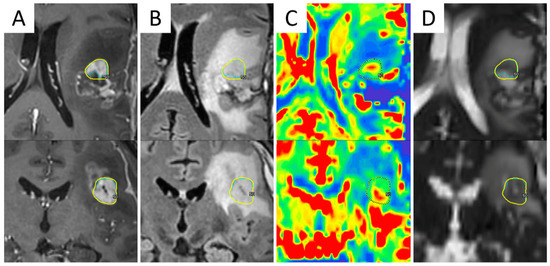

Figure 4.

Example of a volumetric modulated arc therapy (VMAT) sequential boost of radiation to hypoxia-positive recurrent GBM. T2-weighted and contrast-enhanced T1-weighted MRI sequences were acquired along with 64Cu-diacetyl-bis(N4-methylthiosemicarbazone) (ATSM) PET on a hybrid 3T PET/MR scanner, three hours after radiopharmaceutical injection (A,B). 37.5 Gy were delivered in 15 daily fractions to the surgical cavity followed by a boost of radiation (5 Gy) to the 64Cu-ATSM-positive tumor region, indicating chronic hypoxia (C,D).